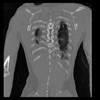

29 CUERPO,CE,Coronal,3.000,CUERPO,Coronal,